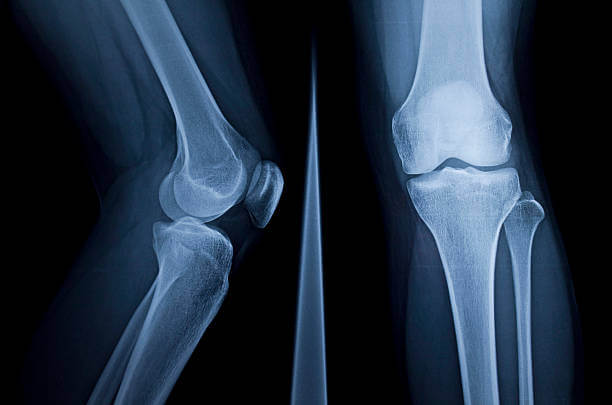

류마티스 관절염은 자가면역체계에 이상이 생기면서 발생하게 되는 질환입니다. 류마티스 관절염은 관절이나 힘줄을 둘러싸고 있는 활액막에 염증이 생기면서 발생하게 됩니다.

통증이 있는 등의 증상이 있을 경우에 발견할 수 도 있지만 혈액검사, 방사선 등을 통해서도 류마티스 관절염이 진단 가능합니다.

류마티스 관절염은 초기에 손가락 관절이나 손목관절에서 많이 생기며 관절염이 진행되면서 팔꿈치, 발목, 어깨, 무릎관절에서도 나타날 수 있는 질환입니다.